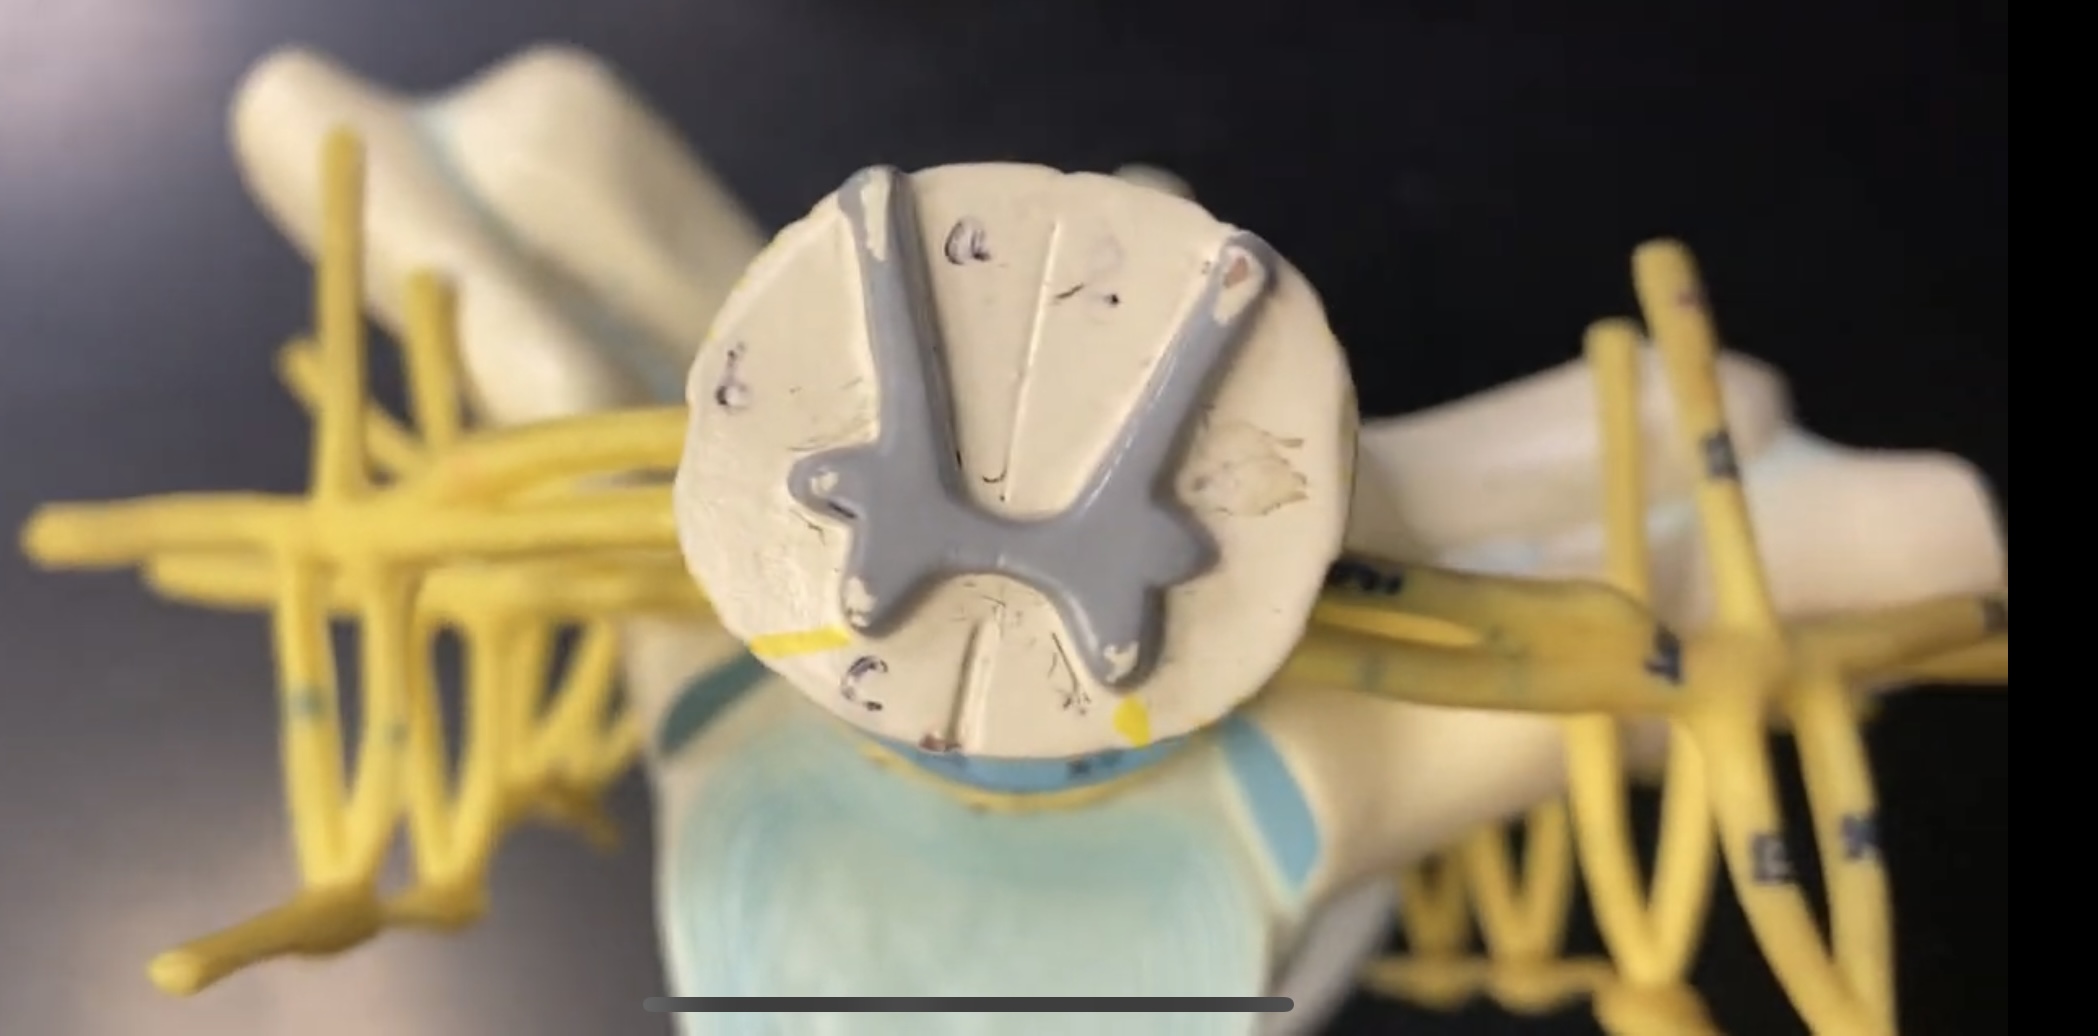

anterior median fissure

posterior median sulcus

posterior (dorsal) horn

anterior (ventral) horn

gray commissure

central canal

anterior column

lateral column

posterior column

white commissure

posterior (dorsal) root

anterior (ventral) root